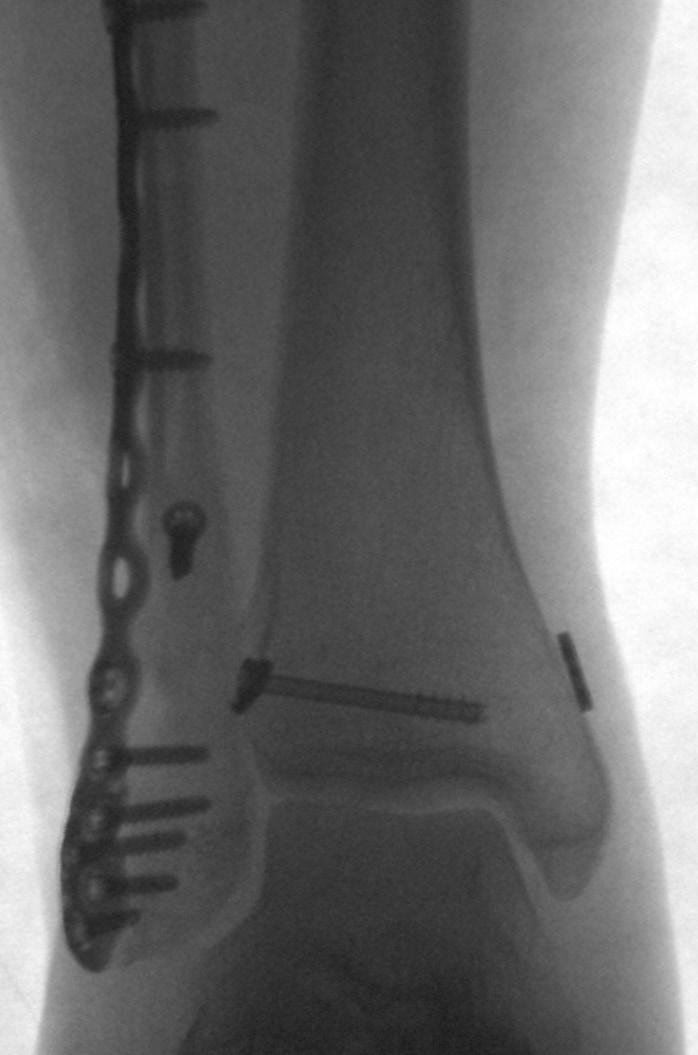

Percutaneous posterolateral malleolus fi xation

Posterior approaches to the ankle are not without morbidity, often causing increased swelling, stiffness and reduction in dorsiflexion due to posterior scar formation compared to direct medial and lateral approaches. Posterior approaches can also limit access to the medial and lateral malleoli and the trajectory of syndesmotic fixation. If posterior metalwork removal is required, approaching this through significant scar tissue can be challenging and causes further stiffness.

Ed Gee Consultant Trauma and Orthopaedics, Salford Royal NHS Foundation Trust

Percutaneous posterior to anterior screw fixation enables a safe method of reduction and stabilisation of the posterolateral fragment without the morbidity of a posterior surgical approach. This then frees the surgeon to perform a more favourable direct lateral approach to the fibula for fixation and syndesmotic stabilisation without having to utilise the posterolateral approach and apply metalwork through the peroneal tendon bed.

Technical aspects of case selection, pre-operative planning, patient position, dissection, reduction,

guidewire placement, screw insertion and radiological checks are all pivotal to perform this safely and effectively.

Mildly displaced posterolateral fragments are selected (Haraguchi 1, Mason 1, 2A and Bartonicek 1, 2). Pre-operative CT is obtained to assess the posterior malleolus fracture and screw trajectory.

The patient is positioned in a lateral position with the injured side up and on an elevating block, placed behind the non-operative leg. This gives a lateral view of the ankle and allows external rotation of the hip to enable mortise view fluoroscopy, access to the anterior ankle for trauma scope and access medially for medial malleolus fixation. Anatomy is marked on the skin using image intensifier and the level of incision is planned to approach the posterior malleolus.

The posterior malleolus should be fixed first to enable proper assessment of joint line and fracture fragment reduction. Once medial and lateral metalwork is in situ this will obscure fluoroscopic assessment of the posterior malleolus. If fibula reduction is required to restore the syndesmosis prior to posterior fixation the fibula can be approached through a direct lateral approach in this position, reduced and held with a clamp or K-wire in a manner that doesn’t obscure fluoroscopic assessment.

A 10mm incision on the lateral edge of the Achilles tendon at the level of the

posterior malleolus and a 10mm tunnel is blunt dissected down to bone using long dissecting scissors. The leg is rotated until the X-ray projection of the posterior malleolus cortex is separate to the posterior cortex of the fibula. A radiolucent depth gauge or 2mm syringe barrel is used as a wire guide to protect the soft tissues. A guidewire is placed on the posterior malleolus cortex by feel and the leg rotated until there is no overlap between cortex and wire to help judge the exact position in relation to the fracture

and to check the wire is on the tibial cortex and not the fibula.

The guidewire is passed into the fragment and the position is checked on the AP image. The fibula is reduced into the incisura with thumb pressure. The leg is then rotated until the fracture plane is visible on fluoroscopy. The depth gauge/ syringe and guidewire are used to joystick the fragment into position and the wire is passed across the fracture. If the fragment requires further inferior translation

the wire can be angled inferiorly so that screw compression will translate the fragment distally. Once the wire is across the fragment, the depth gauge is pushed against the posterior malleolus to check the fragment will compress. Wire position is checked on the mortise view with depth gauge or artery clip against the posterior tibial cortex to assess the exact entry point, ensuring it will not irritate the fibula or syndesmosis.

The near cortex only is drilled, and one unicortical 4mm cannulated partially threaded screw and washer is inserted under image intensifier. As the washer meets the posterior malleolus it should angle to meet the cortical contour of the posterior malleolus, further confirming correct positioning, and the fracture should be seen to compress. If the wire has been angled inferiorly the fragment should reduce more distally by 1mm or so. Final checks are performed, and the percutaneous portal can be closed with skin suture alone. The surgeon is then free to complete necessary fixation of the malleoli and syndesmosis through direct approaches. n